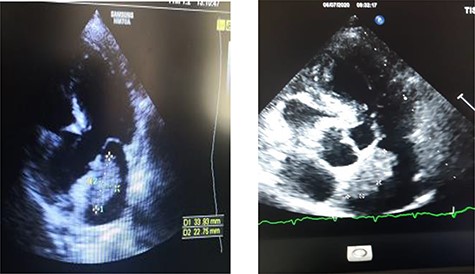

Transthoracic echocardiography showed a left intra-atrial mass with large implantation in the inter-atrial septum measuring 35 × 15 × 26 mm, not interfering with mitral valve movement suggestive of a myxoma (Fig. 2). The left ventricle was neither dilated nor hypertrophied with good global and segmental contractility (LVEF = 69%). Left ventricular filling pressures, right ventricle’s systolic function, were within normal ranges, with minimal mitral insufficiency. Inferior vena cava was not dilated and compliant, and the pericardium was dry. No arterial pulmonary hypertension was found. The preoperative coronary angiography was normal.

Transthoracic echographay: showing a left intra-atrial mass based on a large implantation in the inter-atrial septum.